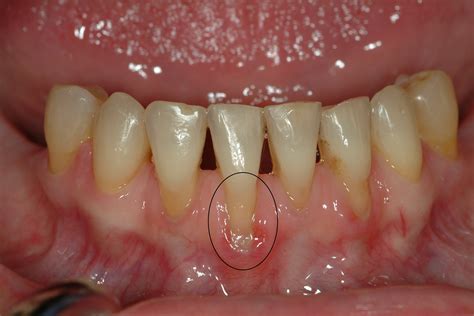

Have you ever noticed your teeth looking slightly longer than usual, or perhaps felt a sudden, sharp sensitivity when consuming a hot cup of coffee or a cold scoop of ice cream? If so, you might be experiencing a common dental condition known as the recession of gingiva. Often referred to simply as gum recession, this process involves the gum tissue surrounding the teeth pulling away, wearing down, or pulling back, thereby exposing more of the tooth or its root. While it might seem like a minor cosmetic issue, it is a significant dental concern that, if left unaddressed, can lead to serious oral health complications, including tooth decay and even tooth loss.

Identifying the Signs and Symptoms

Because the recession of gingiva often occurs slowly, many people do not notice it until the symptoms become obvious. Being proactive is essential for early detection. Watch out for the following warning signs:

• Increased sensitivity to hot, cold, or sweet foods and drinks.

• Teeth that appear longer than before.

• Visible roots of the teeth.

• Gums that are red, swollen, or bleed easily after brushing or flossing.